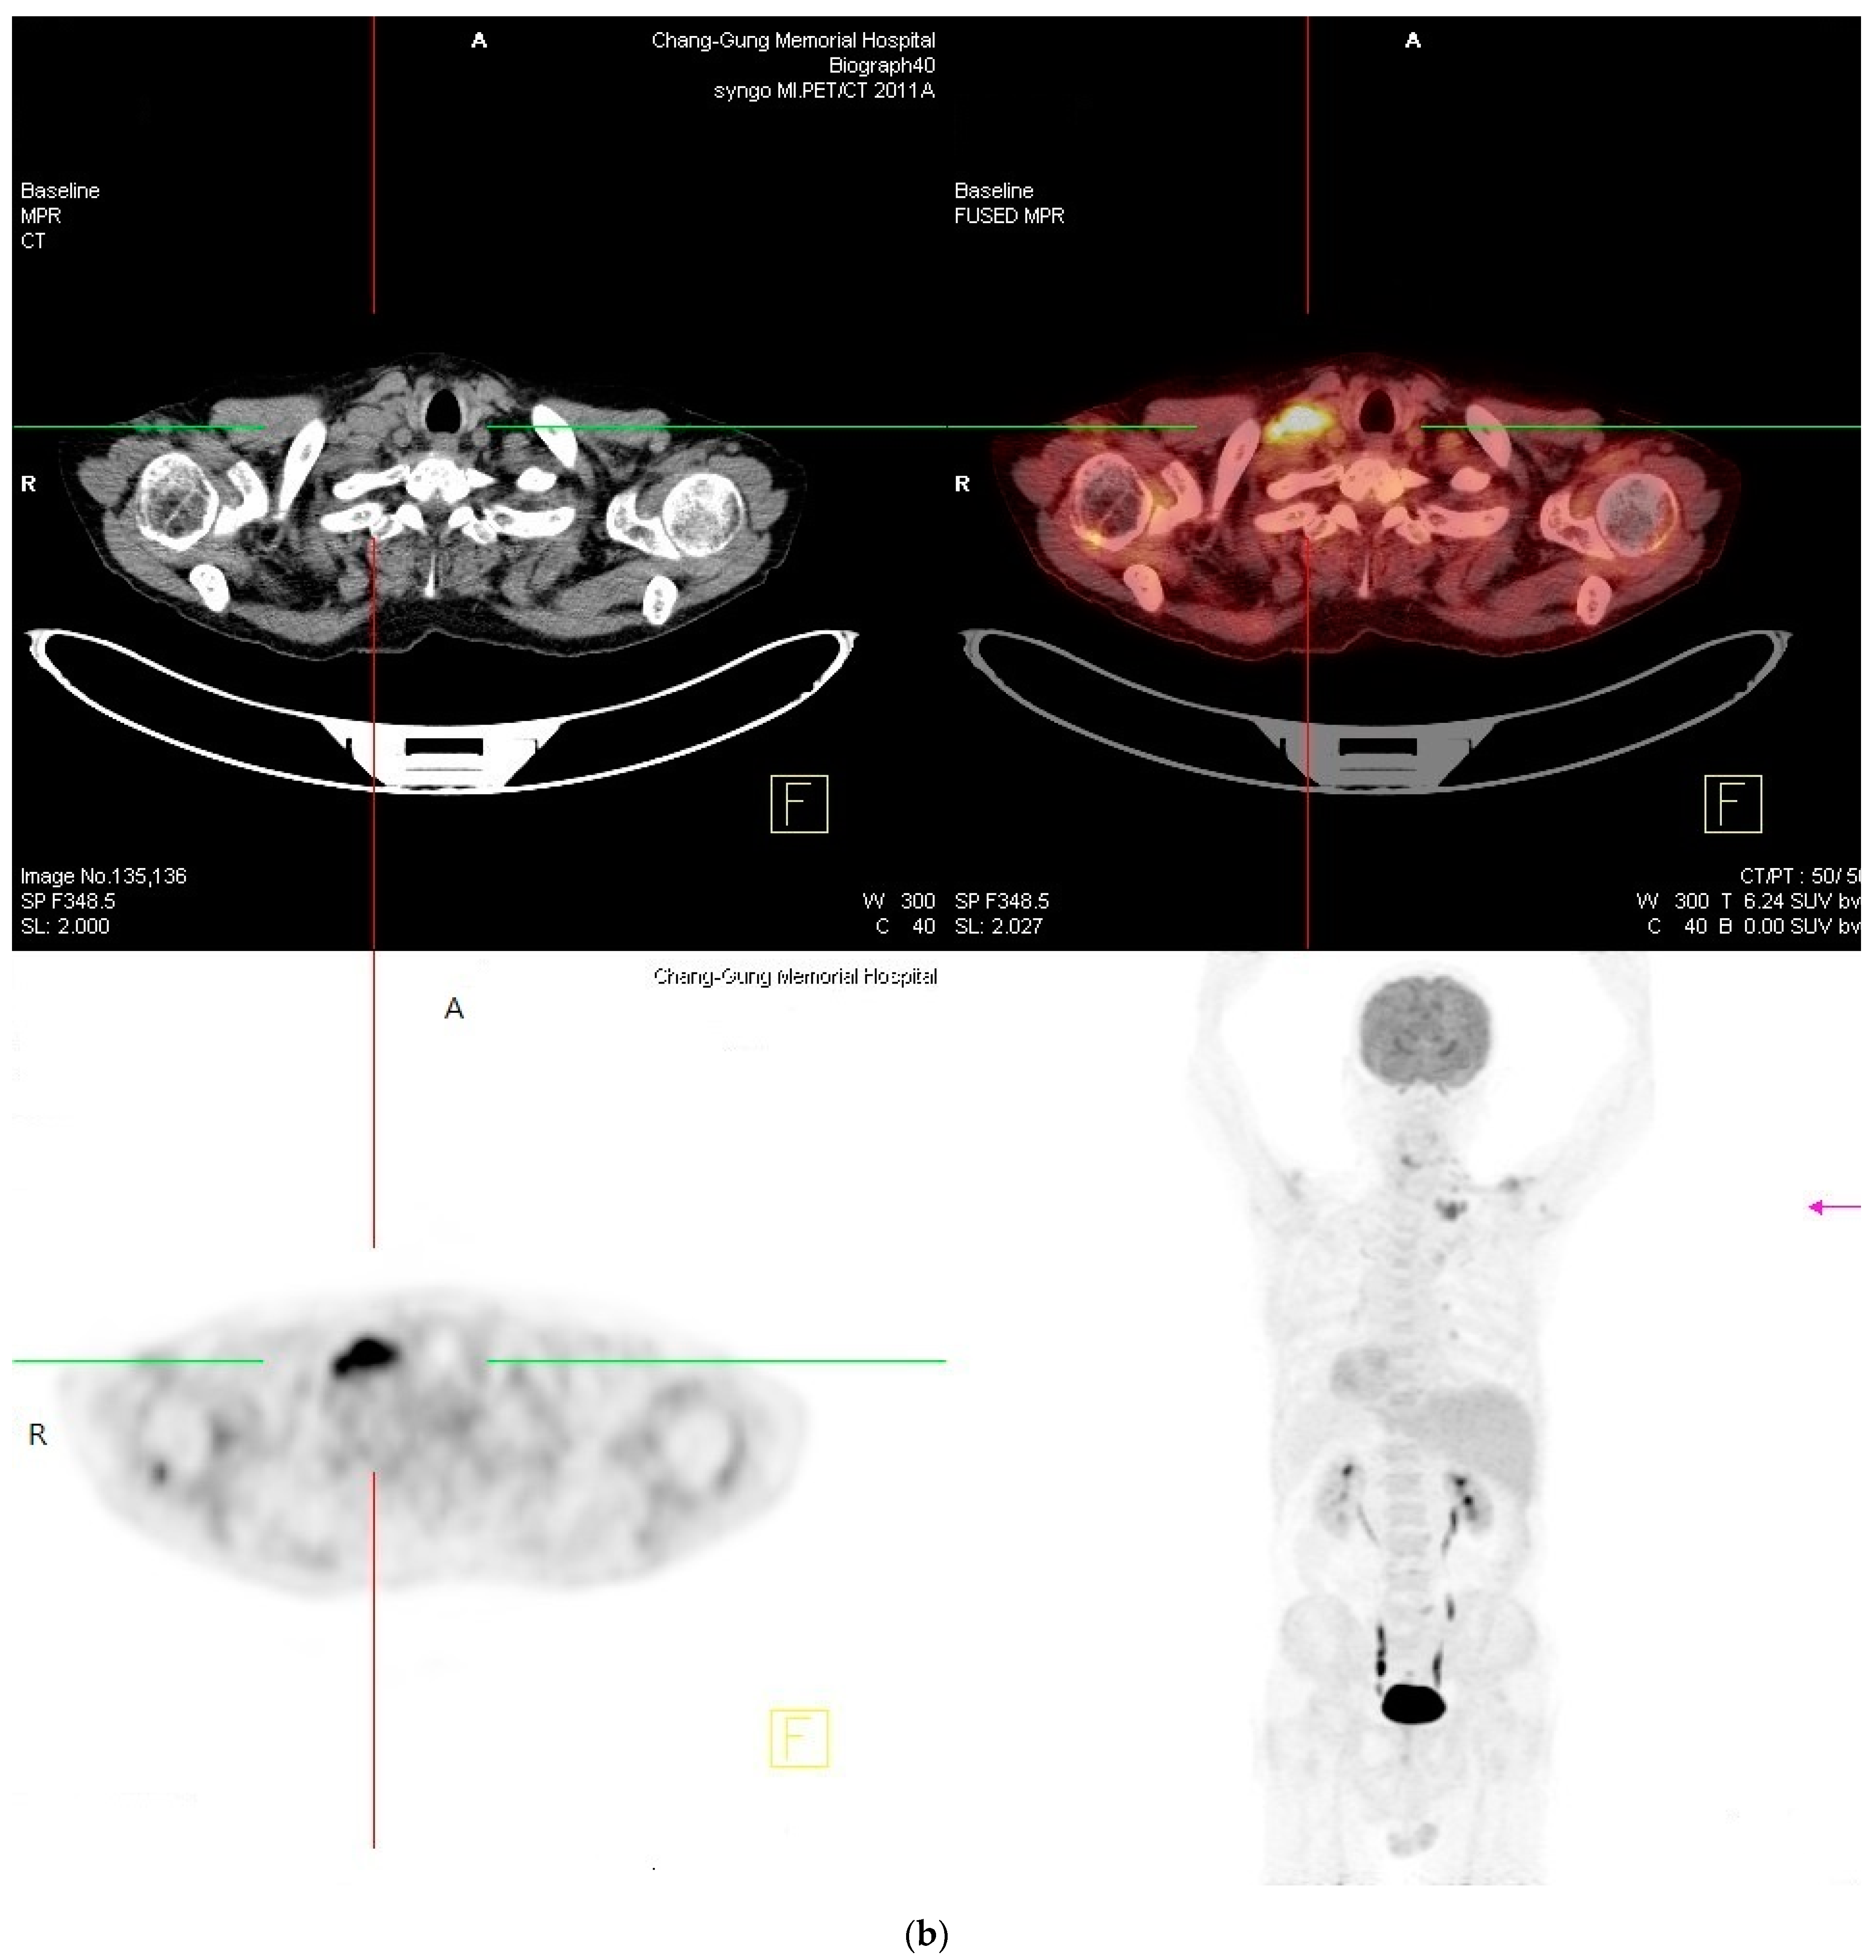

2. Case Report